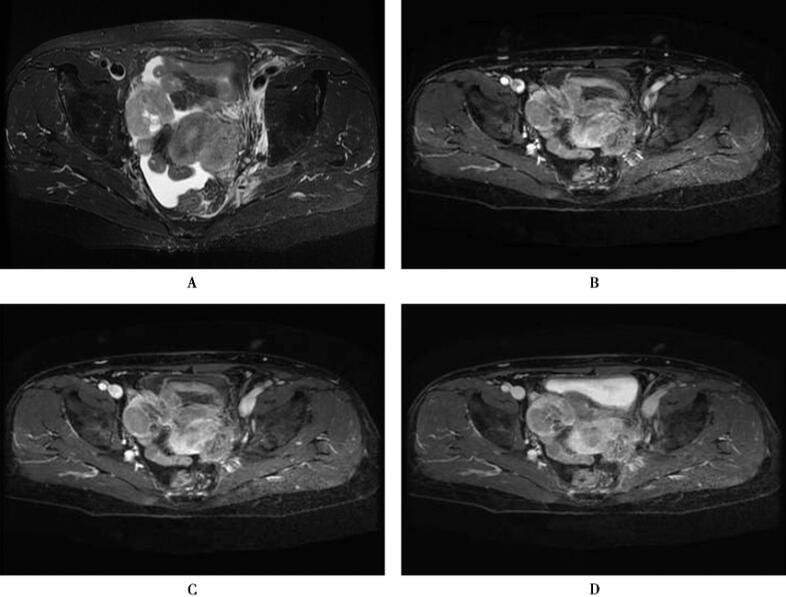

图1卵巢低分化浆液性腺癌

T1WI(A)显示双侧附件等信号肿块,T2WI(B)肿块呈稍高信号,增强扫描(C,D)肿块不均匀强化

卵巢癌在MRI上的表现不同,囊实性的肿瘤最多见,也可以表现为完全囊性或者实性,像本例的实性肿块可呈等信号,其内坏死时T2WI呈高信号,增强扫描能够区分肿瘤的实性部分、坏死部分以及网膜和腹膜的种植转移。MRI诊断的优势在于确定盆腔肿瘤的起源,并且进一步区分肿瘤性和非肿瘤性病变,良性与恶性肿瘤,卵巢原发与转移性肿瘤在MRI上不易区分,在检查时要注意作为原发病灶的消化道有无异常改变,Krukenberg瘤常为双侧性,多为实性,此有助于诊断。